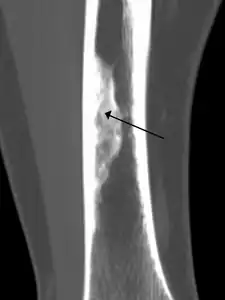

X-ray of nonossifying fibroma of distal tibia.

Diagnosis is by X-ray or MRI, usually when investigating a person for something else.[3] Medical imaging typically shows a well marginated radiolucent lesion, with a distinct multilocular appearance, sometimes looking like bubbles.[3] It is usually around 1-2cm in size, but be as large as 7cm.[4] They consist of foci consist of collagen rich connective tissue, fibroblasts, histiocytes and osteoclasts.[3] Usually no treatment is required.[4] Surgical curettage and bone grafting may be required if it is large.[4]

It is usually iagnosed by x-ray or MRI, when investigating another problem.[1] The tumor presents as a well defined radiolucent lesion, with a distinct multilocular appearance, sometimes looking like a "soap bubble".[2] If small and no symptoms, then biopsy is not needed.[1]

The cause is unknown.[1] The foci consist of collagen rich connective tissue, fibroblasts, histiocytes and osteoclasts. They originate from the growth plate, and are located in adjacent parts of the metaphysis and diaphysis of long bones, most often of the legs.[3]